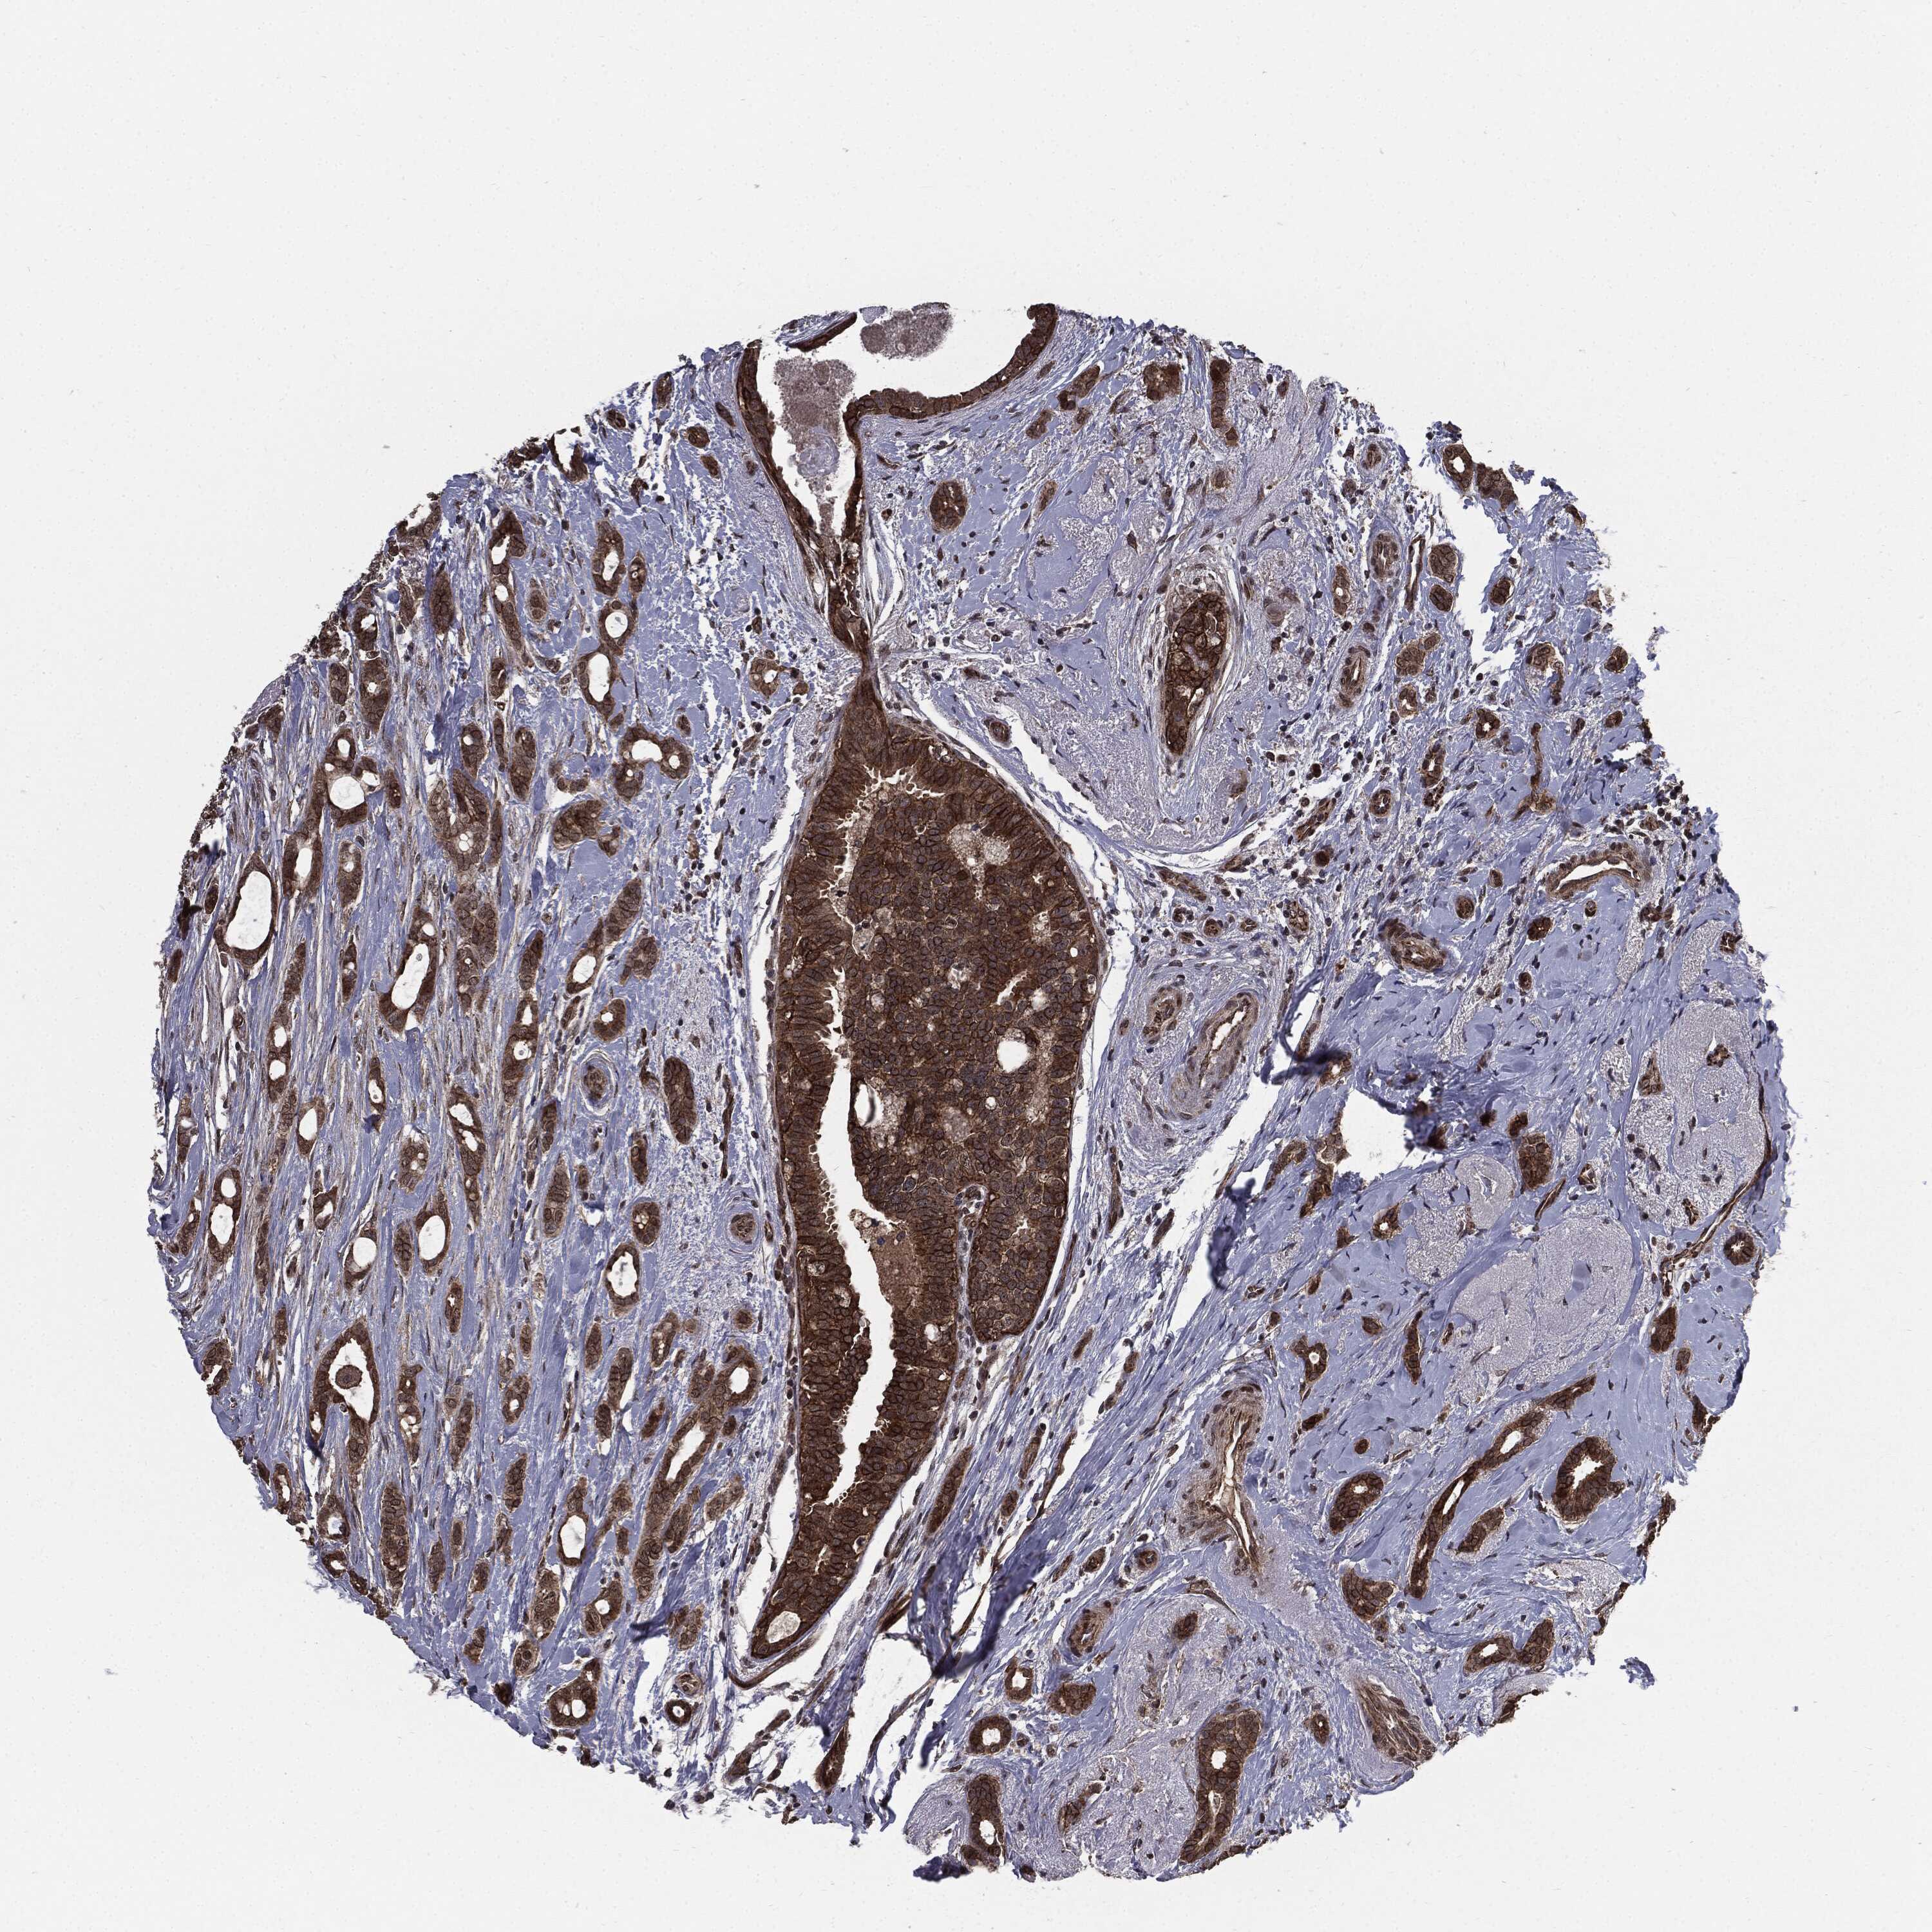

CANCER BREAST CANCER Show tissue menu

BRCA TCGA BRCA VALIDATION PROTEIN EXPRESSION

ANTIBODIES

AND

VALIDATION